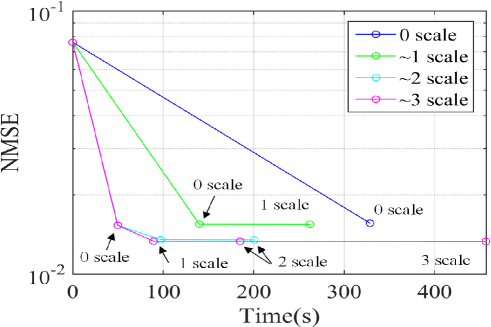

In order to show the importance of the pyramidal decomposition, Fig. 7 plots the computational time versus NMSE values of single coil brain data by changing the number of decomposition levels. As discussed before, the maximum decomposition level is determined by the acquired low frequency components and the annihilating filter size. In this data set, k-space dimension was and the annihilating filter size was , and k-space data around zero frequency were acquired. By converting the Hankel matrix dimension in (88) for the -scale, the number of rows should not be smaller than the number of columns; so we should impose constraint

where is the scale. This provides , and the maximum scale becomes 2. Fig. 7 showed that the performance gain increases as a scale increases; as expected, for , the performance improvement was negligible. Therefore, the maximum scale was determined as .